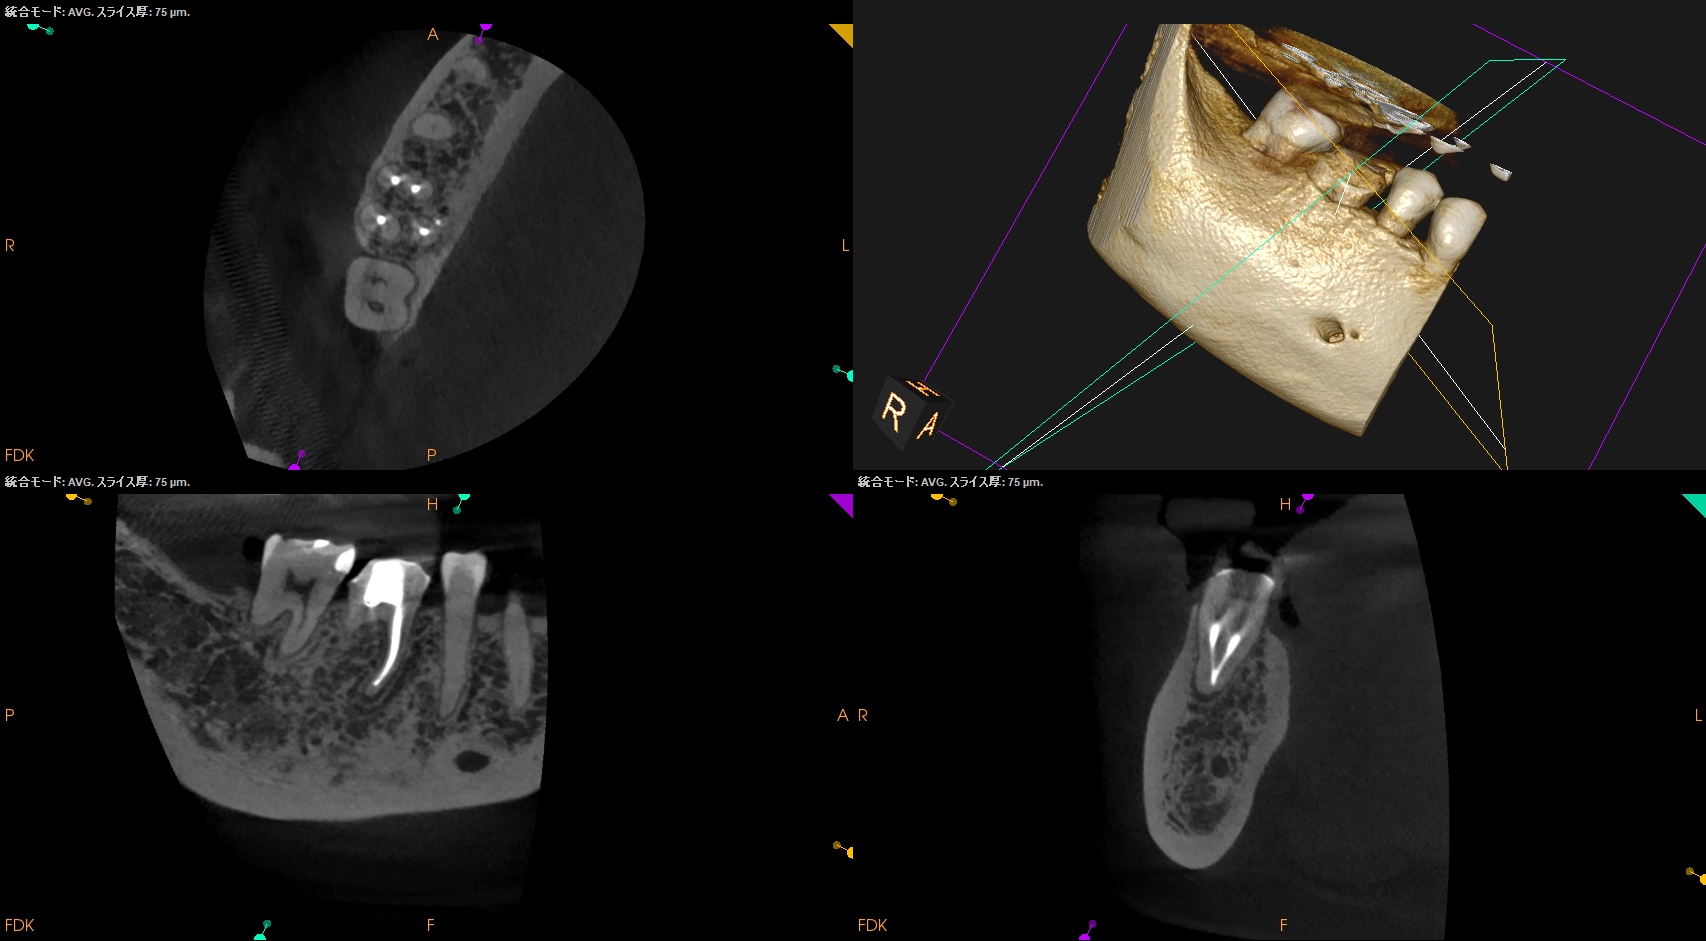

支台築造後にPA, CBCTを撮影した。

MB

ML

D

Radix

問題はないだろう。